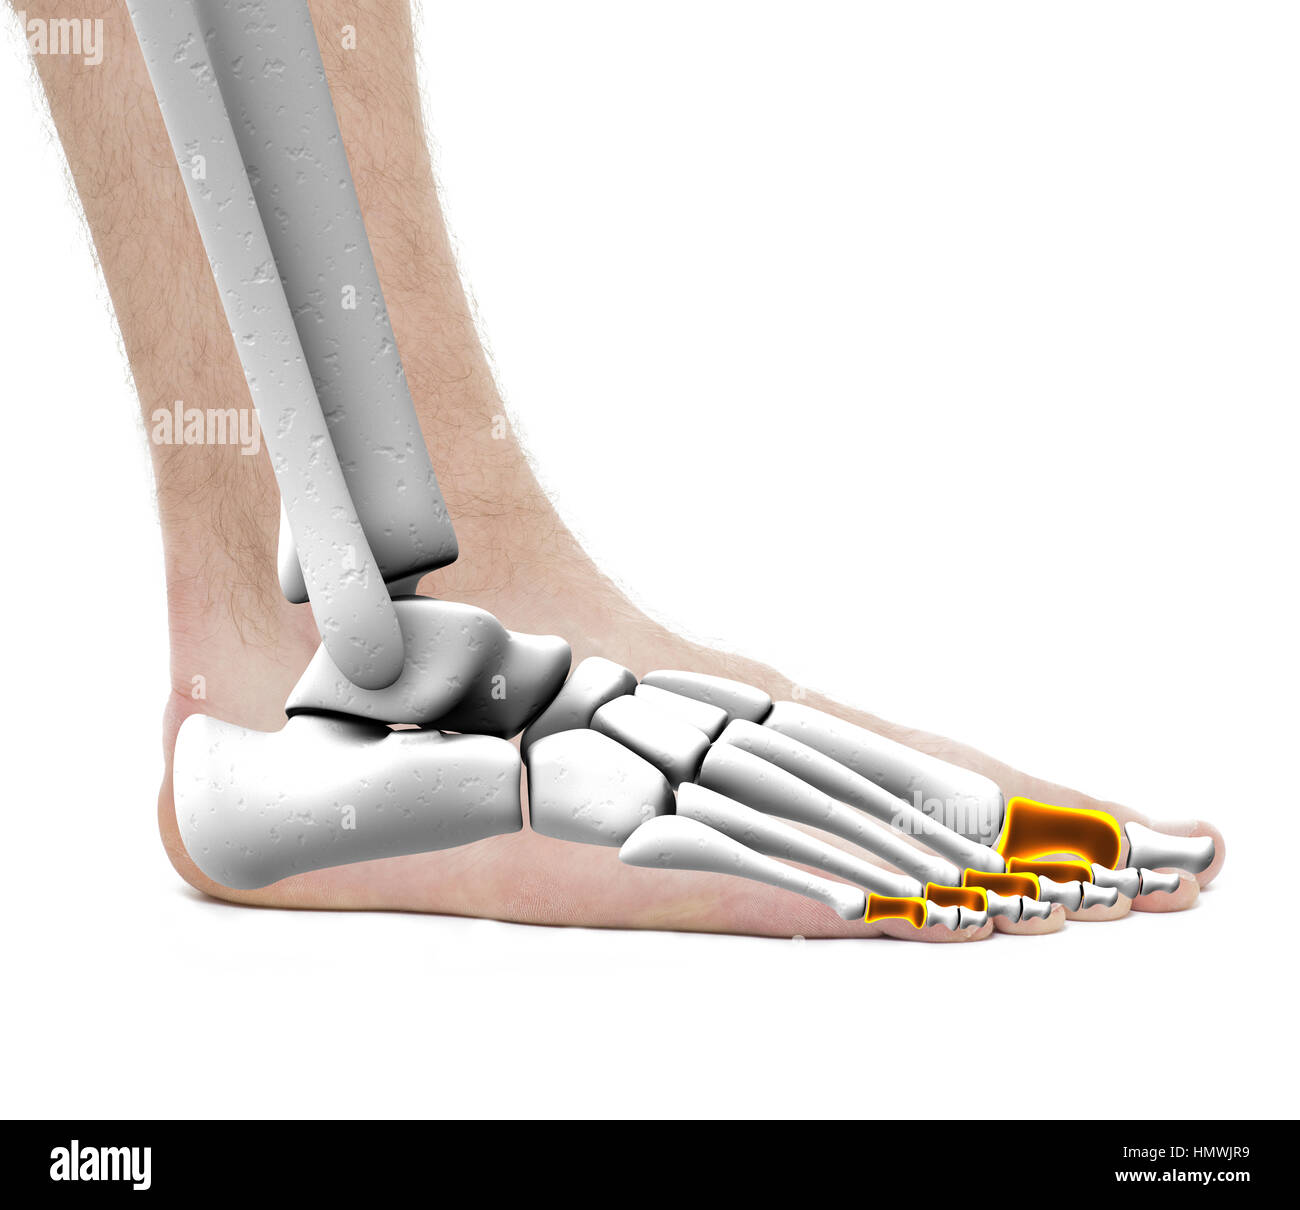

RF2R3WKY1–Illustration médicale des principales parties des os du pied en vue latérale, avec annotations.